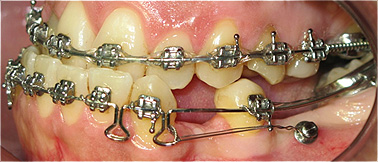

Correção da mordida cruzada anterior, com microimplante, após 6 meses de tratamento.

![]() |